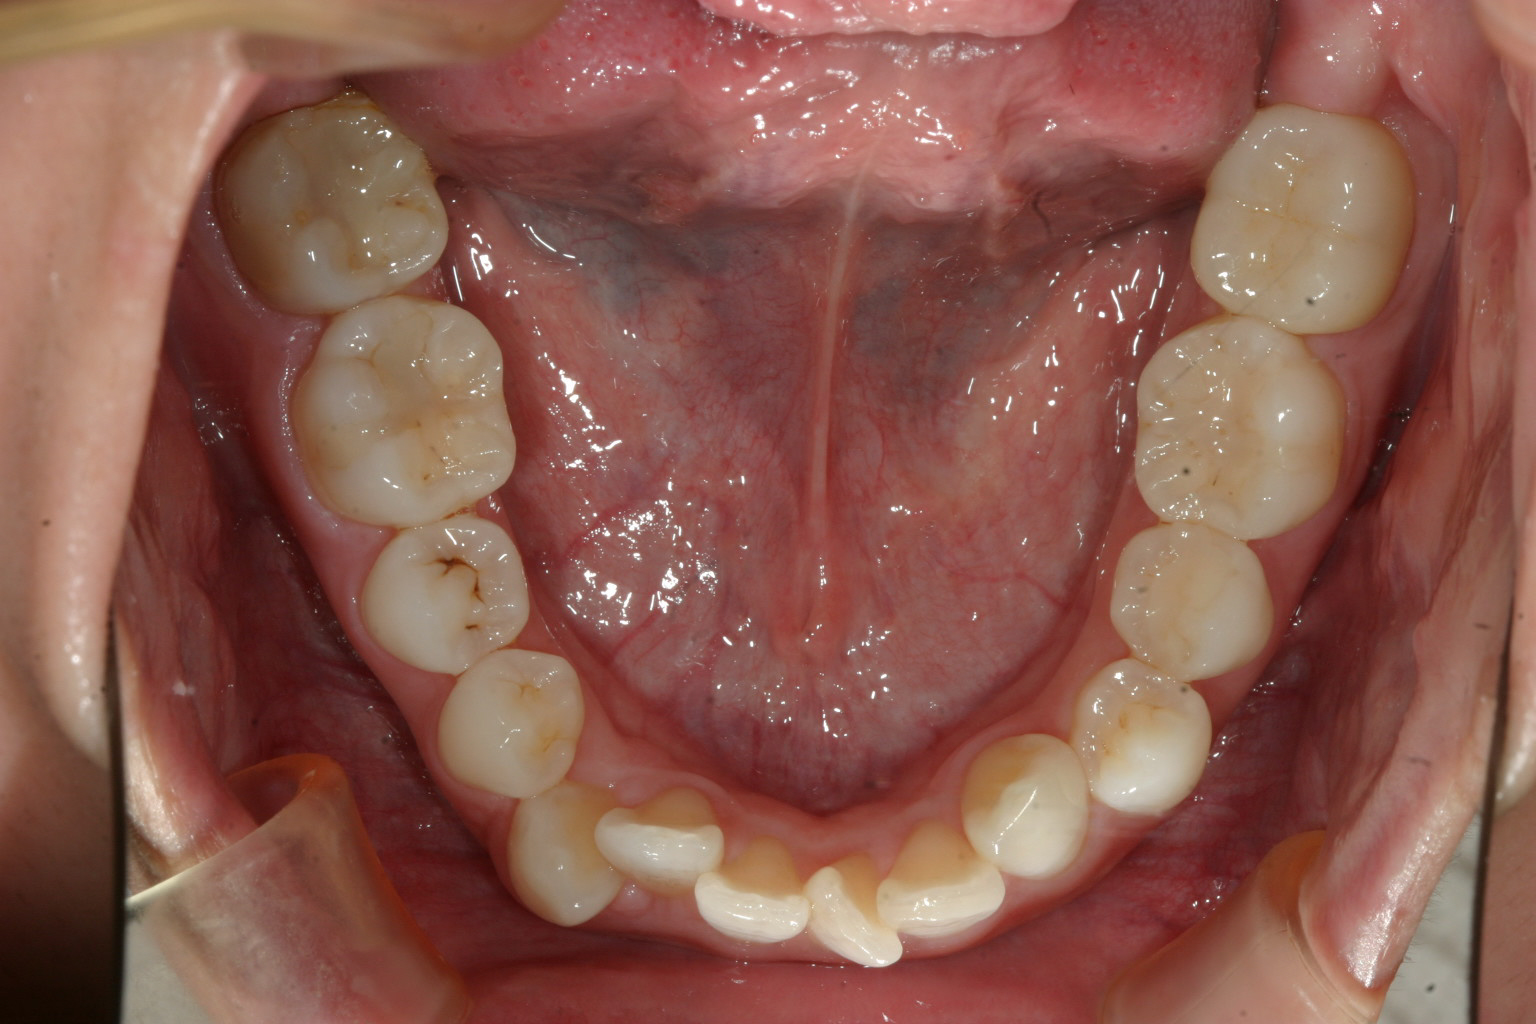

下顎も同じくアーチが狭く叢生が見受けられます。

下顎も叢生が取れて綺麗に並びました。